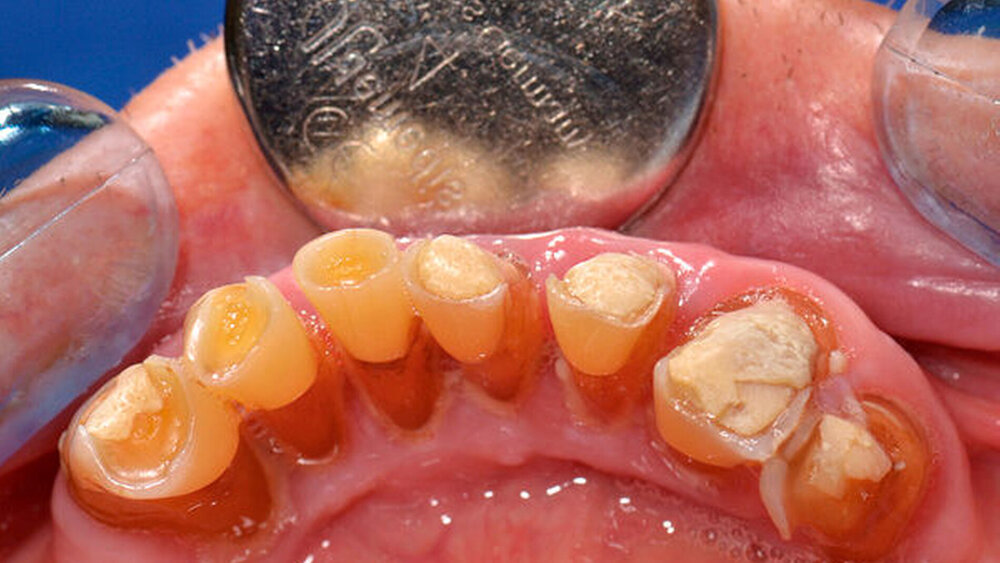

Die klinische und radiologische Untersuchung (Abbildungen 1 und 2) zeigte einen zahnlosen Oberkiefer sowie eine nicht erhaltungswürdige, stark parodontal geschädigte anteriore Restbezahnung im Unterkiefer. Aufgrund der bekannten schweren Hämophilie B (Faktor-IX-Aktivität < 1 Prozent) erfolgte die Vorstellung des Patienten in der betreuenden Gerinnungsambulanz in der Abteilung für Hämatologie, Onkologie und Palliativmedizin der Universität Rostock. In interdisziplinärer Absprache wurde unter Berücksichtigung des operativen Behandlungsbedarfs ein Faktorsubstitutionsplan für den Patienten erstellt (Tabelle). Aufgrund der Komplexität des Behandlungsprotokolls fand die weitere Therapie unter stationären Bedingungen statt.

Am Aufnahmetag wurde die erste Substitution mit 1800 I.E. humanem Blutgerinnungsfaktor IX (Berinin®, CSL Behring, Marburg) mit anschließender Faktor-IX-Aktivitätskontrolle (angestrebte Aktivität: 20 Prozent) zur Kontrolle des Therapieansprechens durchgeführt. Nach Rücksprache mit den Kollegen der Gerinnungsambulanz konnte die geplante Extraktion der Zähne 43, 42, 41, 31, 32, 33 und 34 am Folgetag unter erneuter vorheriger Substitution und Faktor-IX-Aktivitätskontrolle (Zielwert > 60 Prozent) sowie antibiotischer Abschirmung (i. v. 3 x 3 g Ampicillin/Sulbactam) durchgeführt werden.